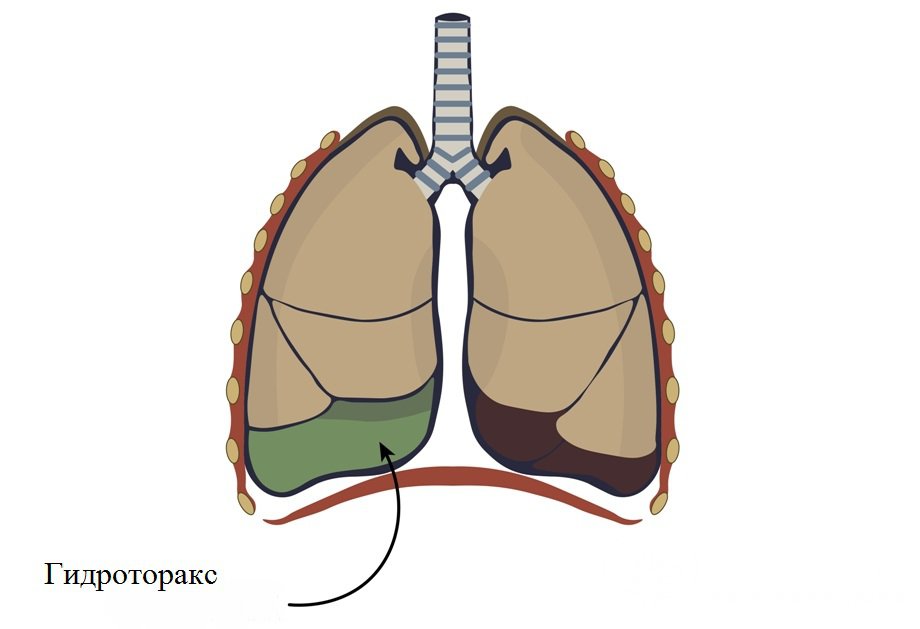

Гидроторакс – это скопление невоспалительной жидкости (транссудата) в плевральной полости.

При гидротораксе количество жидкости в плевральной полости значительно увеличивается (до 1 л и более), что сопровождается развитием характерной симптоматики.

Скопление жидкости (транссудата) в плевральной полости при гидротораксе

Скопление жидкости (транссудата) в плевральной полости при гидротораксеПричины